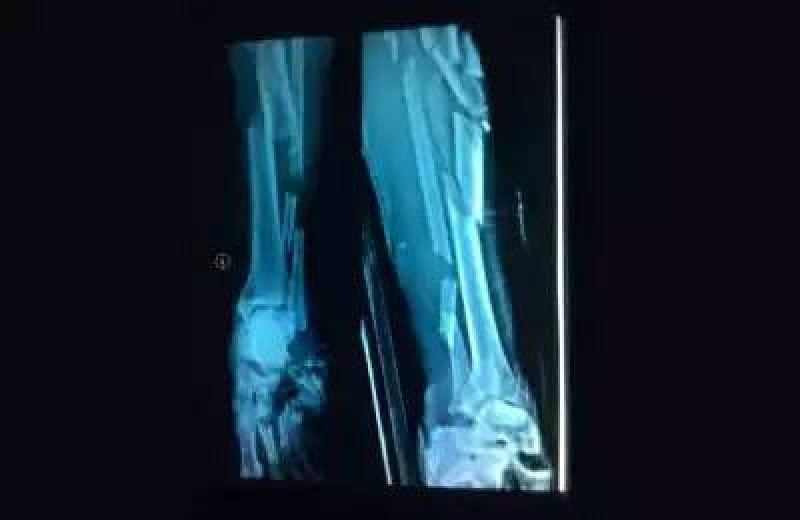

หลังนักบิดเจ้าถิ่นเข้าเส้นชัยเป็นอันดับแรก แต่กลับรถความเร็วลงกระทันหัน เพื่อโบกมือทักทายแฟนๆ ทำให้นักบิดชาวไทย ที่ไล่แย่งอันดับ 5 กับ โทโมยาชิ นักบิดชาวญี่ปุ่น ที่อัดความเร็วช่วงสุดท้ายมา ชนเข้ากับ ฟาดลี อย่างจัง ทำให้กระดูกขาซ้ายของนักบิดเจ้าถิ่นแตก ขณะที่ จักรกฤษณ์ ได้รับบาดเจ็บที่นิ้วก้อยขวาและสลบคาสนาม จนถูกนำตัวส่งโรงพยาบาลใกล้สนามแข่งทั้งคู่

ล่าสุดมีรายงาน อาการของ จักรกฤษณ์ ดีขึ้นมาก แต่ยังต้องพักฟื้นสักระยะ และถูกส่งไปรักษาตัวที่โรงพยาบาลในกรุงจากาตาร์แล้ว โดยคาดว่าจะสามารถลงแข่งสนามต่อไปที่ประเทศญี่ปุ่นได้ทันเวลา เช่นเดียวกับอาการของ ฟาดลี เพจ Astra Motor Racing Team ซึ่งเป็นทีมสังกัดของ ฟาดลี ได้ออกแถลงการณ์วันนี้ (8 มิ.ย. 58) ว่า อาการของ ฟาดลี ดีขึ้น และทีมแพทย์ประสบความสำเร็จในการผ่าตัดเป็นอย่างดี